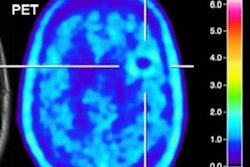

When glioma results are inconclusive on MRI, clinicians should consider fluoroethyl-tyrosine (FET)-PET for more definitive results and to differentiate between tumor progression and treatment improvement, according to a study published online September 13 in the Journal of Nuclear Medicine.

German and Dutch researchers found that the FET-PET achieved sensitivity, specificity, and accuracy of 70% or greater and helped solve mysteries left by MRI.

This retrospective study included 127 patients (median age, 50 years ± 12 years; range, 20-78 years) who were referred for evaluation of tumor progression and treatment-related changes. Of those subjects, 125 people (98%) previously were diagnosed with grade II-IV gliomas, while the two other patients were treated for suspected glioma without prior biopsy. FET-PET imaging was performed on either a standalone scanner (Ecat Exact HR+, Siemens Healthineers) or PET/MRI system (BrainPET, Siemens) and began 0 to 50 minutes after injection of 3 MBq/kg based on body weight.

Maurer and colleagues were able to diagnose tumor progression in 94 patients (74%) and treatment-related changes in 33 cases (26%). Receiver operating characteristic (ROC) analysis showed an optimal FET maximum tumor-to-background ratio (TBRmax) cutoff value of 1.9 for differentiating between tumor progression and treatment-related changes. That benchmark resulted in sensitivity of 70%, specificity of 71%, and accuracy of 70%.